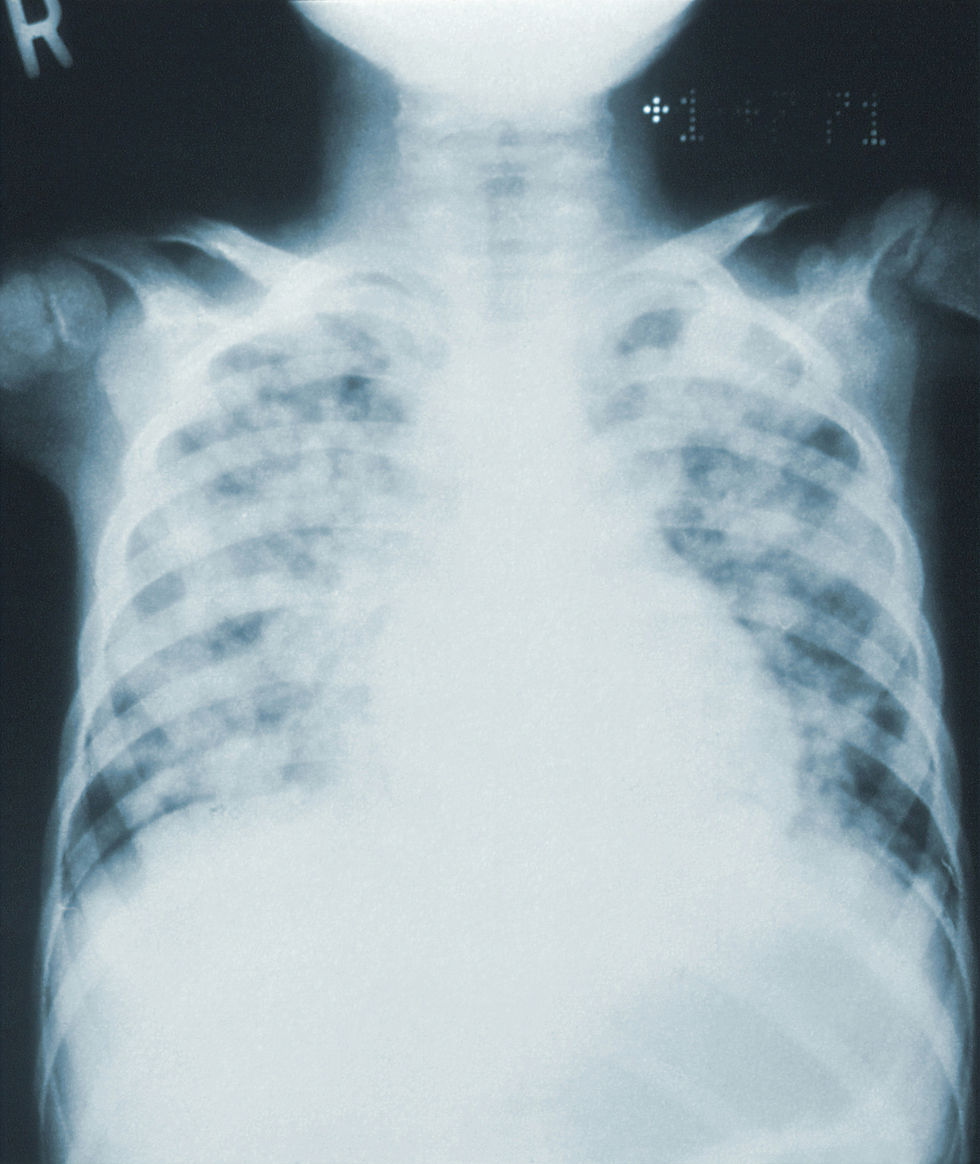

In some cases, patients may develop a depression in the chest wall. The indentation can compress the heart and lungs, ultimately leading to respiratory symptoms such as chest tightness, palpitations, and shortness of breath.

Chest wall abnormalities: Bony structure abnormalities involve the absence and deformation of ribs and costal cartilages, which can manifest as chest wall depression. Soft tissue abnormalities involve developmental anomalies of the pectoralis major, pectoralis minor, and breast tissue, which can present as chest wall asymmetry and breast hypoplasia.